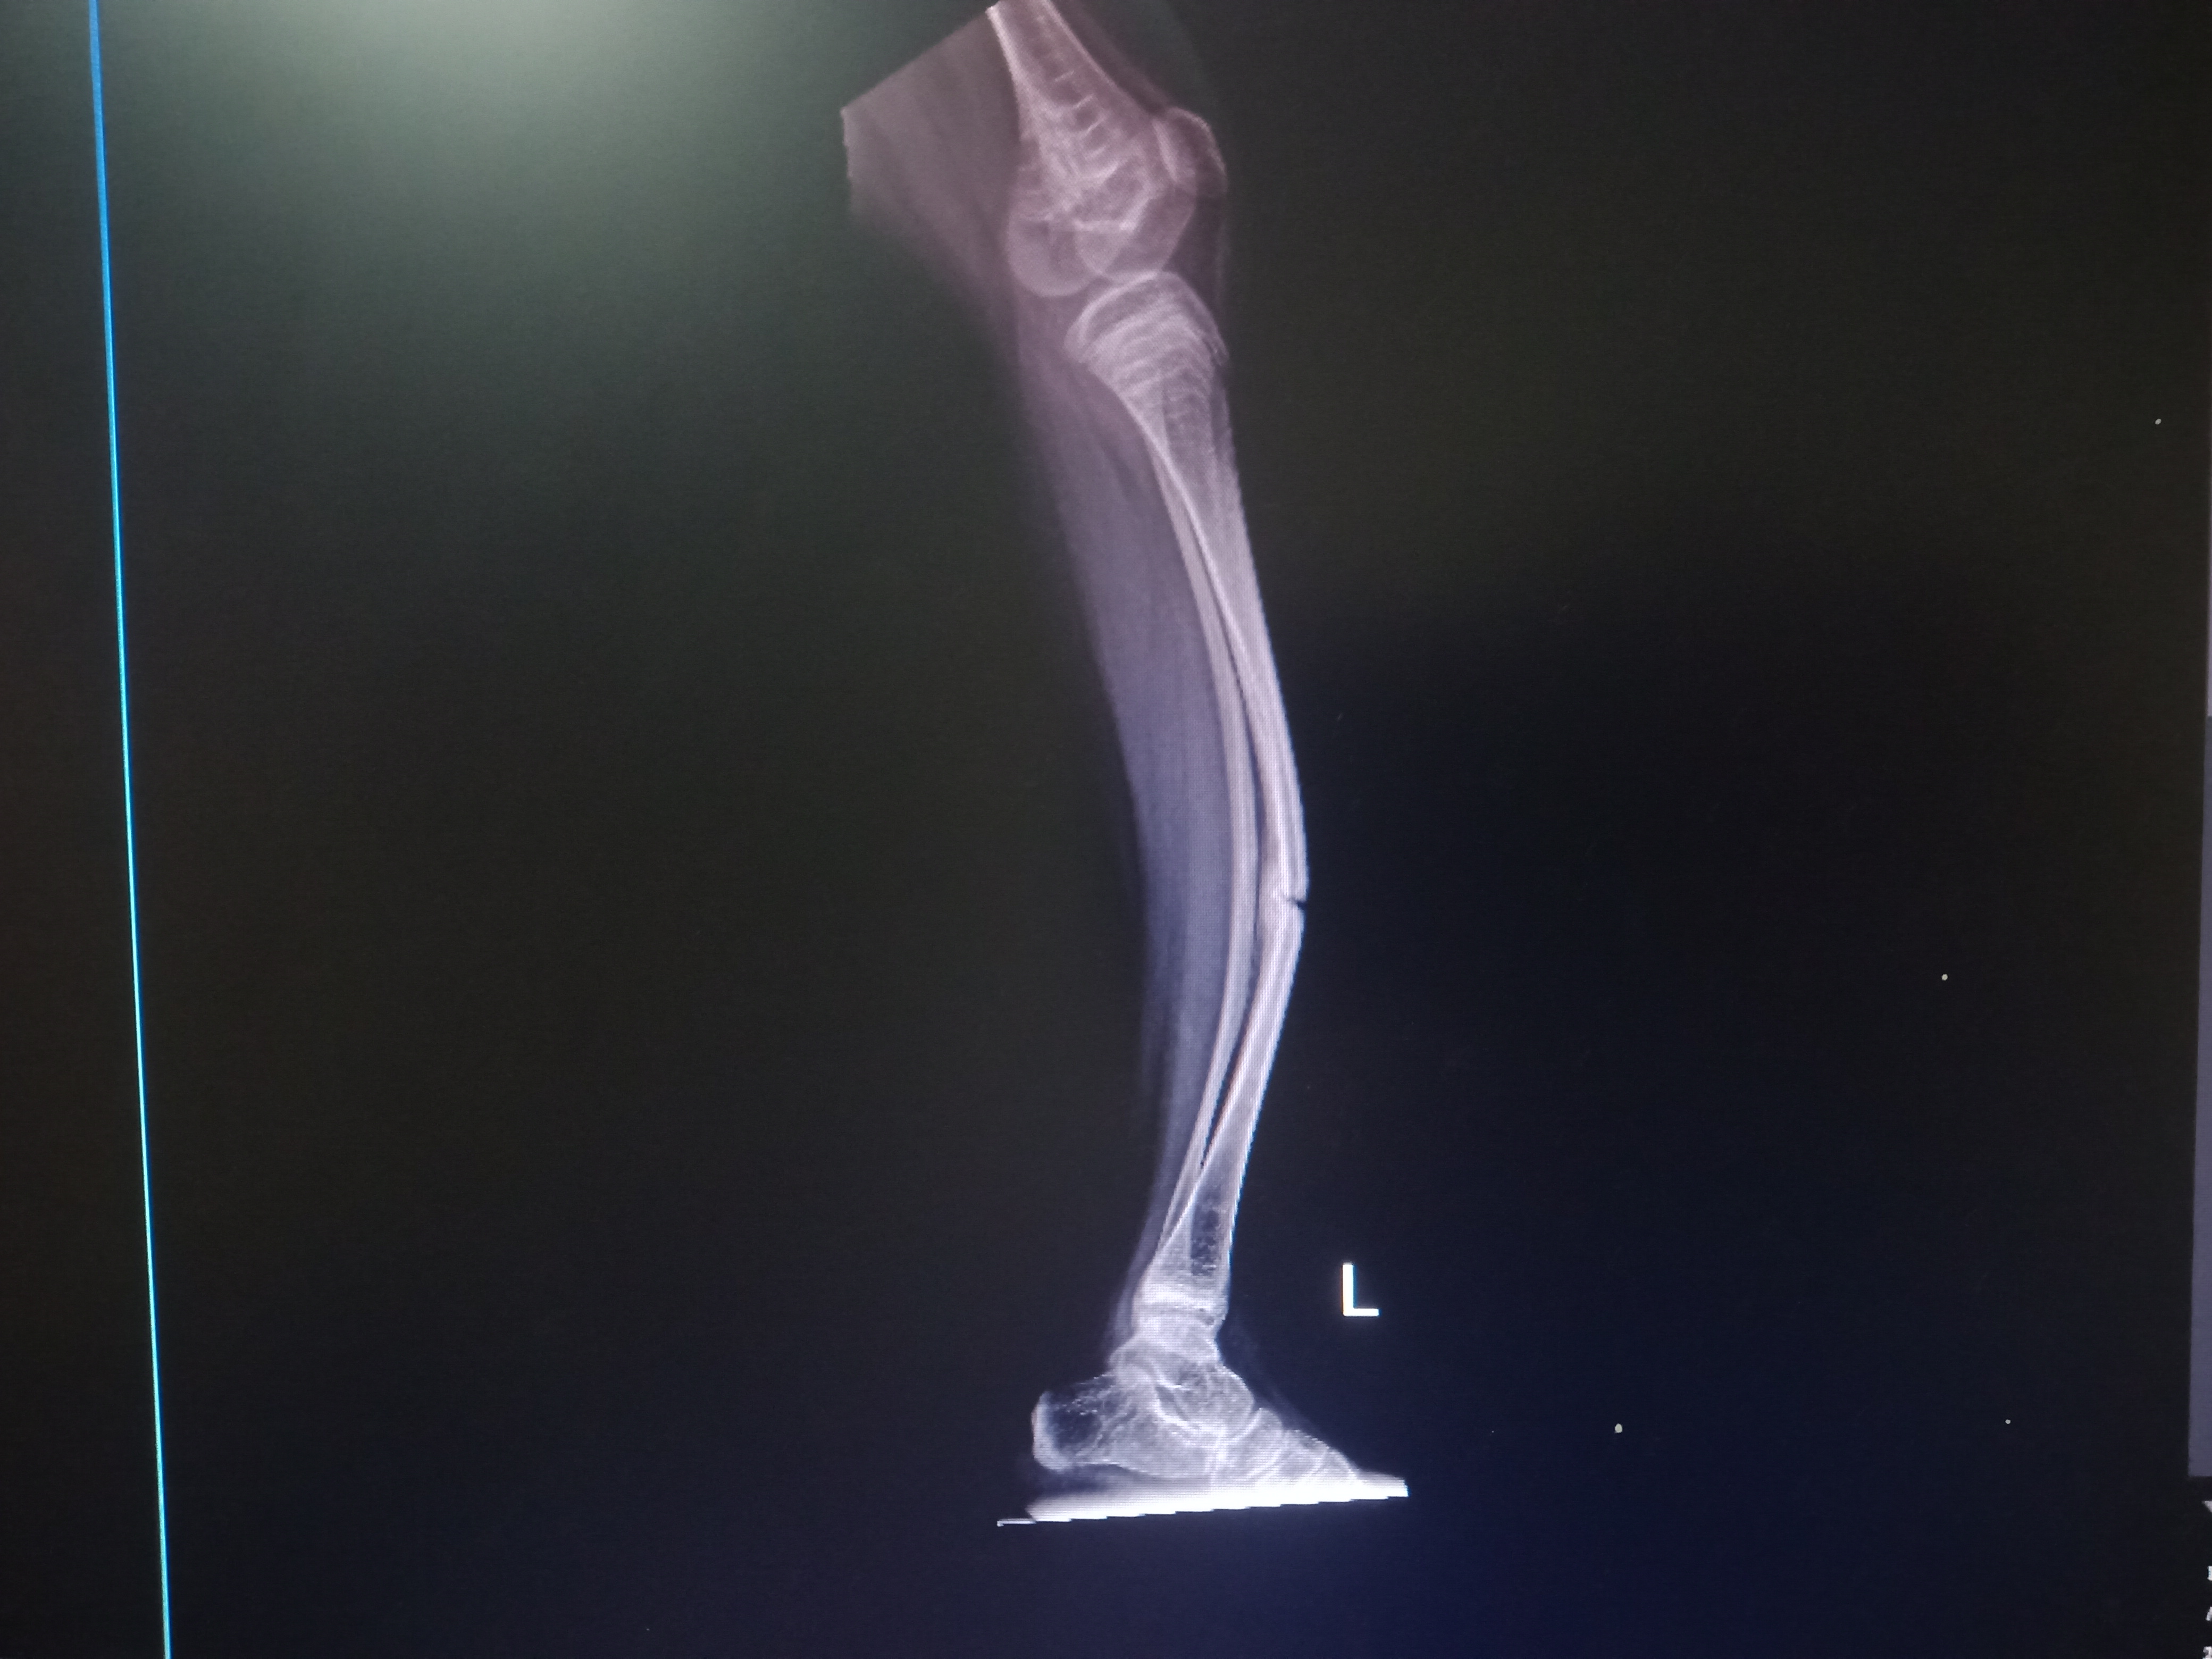

Pada tanggal 2 Maret 2023, anakku kontrol lagi ke poli orthopedi di RSCM untuk melihat hasil bone survey. Ternyata, ada bagian tulang yang masih belum menyatu. Maka dari itu, tim dokter melakukan tindakan pemasangan gips.

Sebenarnya, anakku disuruh melakukan operasi pasang pen. Tapi, karena anakku tidak berani dan nangis, maka dokter memberi waktu untuk aku membujuknya agar berani untuk dioperasi. Karena, menurut tim dokter kaki kiri dan kanan anakku sudah bowing (bengkok) dan mengkhawatirkan.

Pada tanggal 15 Februari 2023, Anza kontrol ke faskes satu klinik Bhakti Rahayu. Keesokan harinya, Anza kontrol ke faskes dua RS Medika bogor.

Setelah itu, pada tanggal 23 Februari 2023, Anza kontrol ke poli orthopedi di RSCM dan dilakukan pemeriksaan radiologi bone survey. Hasilnya akan keluar pada tanggal 2 Maret 2023 mendatang, dan dilanjutkan pemeriksaan ke poli pediatrik rehab medik pada tanggal 9 Maret 2023 untuk dirawat inap alendronate.